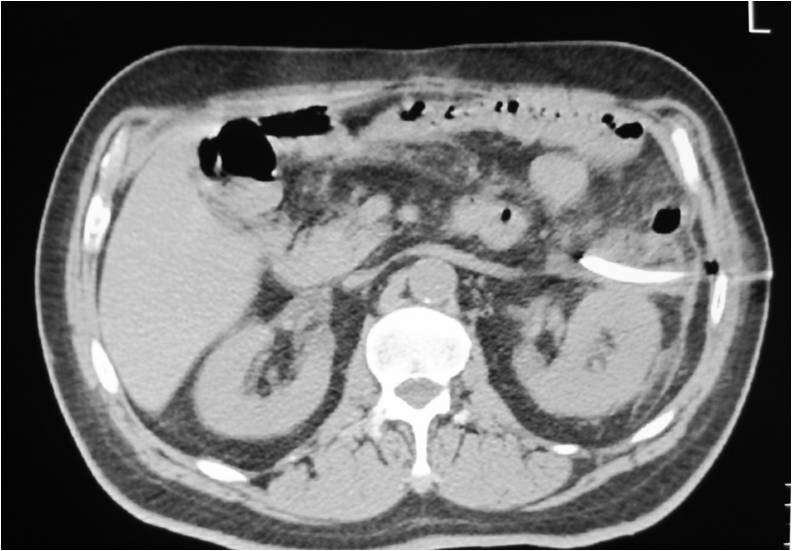

- Abscess post right hemicolectomy

- Successful placement and drainage